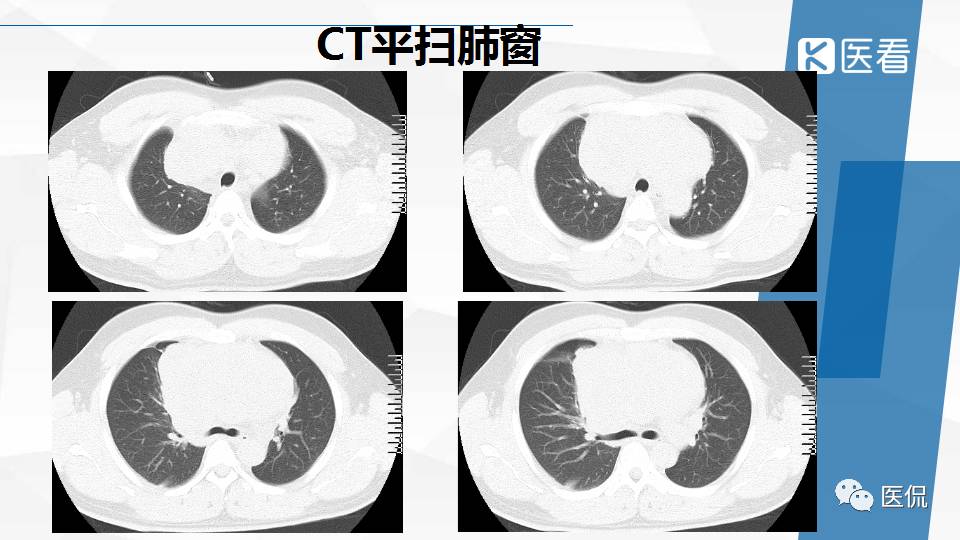

纵隔精原细胞瘤案例 (精原细胞瘤影像表现与鉴别诊断)

精原细胞瘤ct影像,精原细胞瘤影像特征